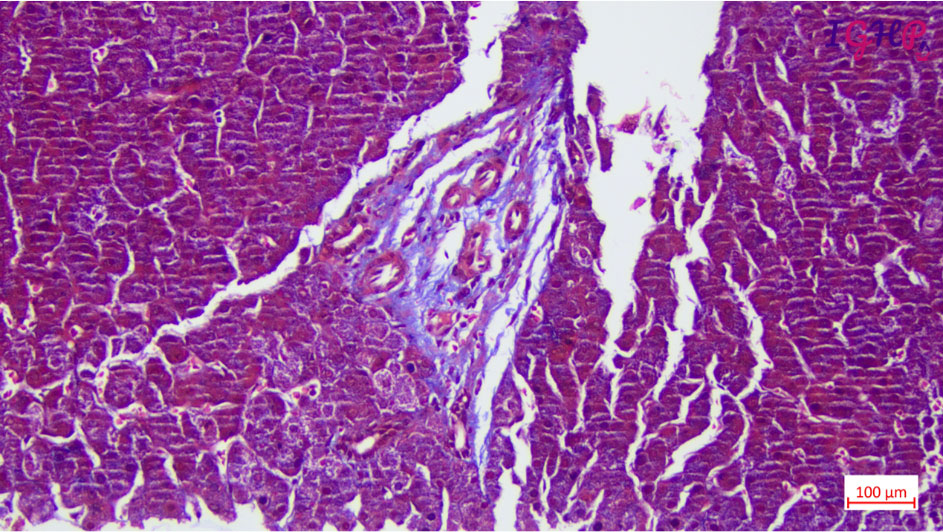

Special Stain Performed-

MT, Orcein and Reticulin stains performed showed maintained liver cell plate network with presence of thin delicate blind ended septae around few of the portal tracts.